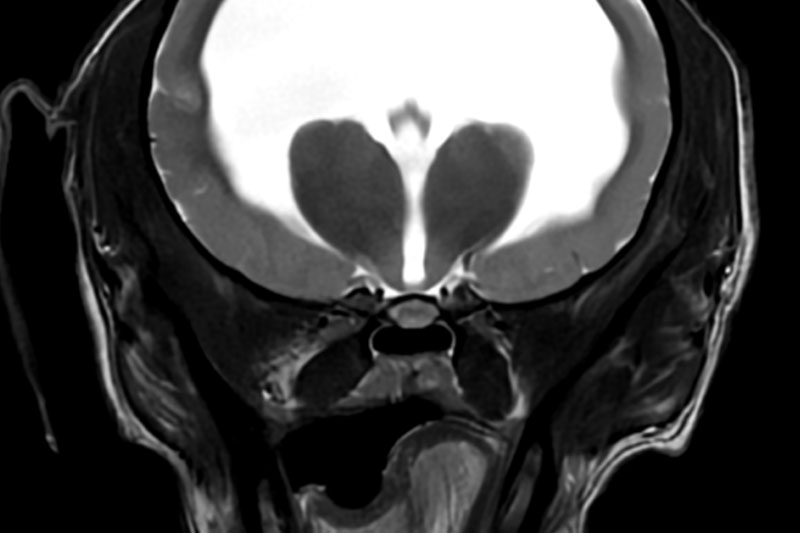

| 뇌/두개강 | 뇌종양, 뇌염, 수두증, 간질, 뇌출혈, 시신경 이상 등 |

| 척수/신경계 | 디스크 탈출, 척수압박, 척수염, 척수종양 등 |

| 관절/연부조직 | 십자인대 손상, 슬개골 탈구, 인대/연골 이상, 관절염 등 |

| 복부 연부조직 | 간, 췌장, 신장, 부신 등 내부 장기의 정밀 촬영 |

| 종양 조직 | 종양의 성질, 침윤 범위, 주위 조직과의 관계 확인 등 |